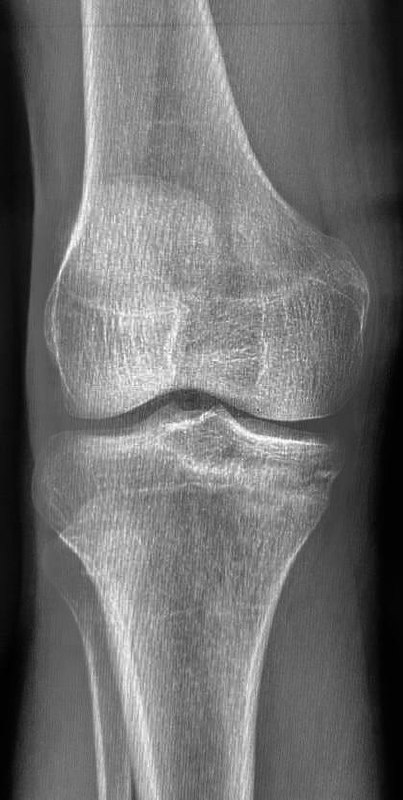

Тот случай, когда на рентгене видно то же, что и на КТ.

Переломы от перегрузки (маршевые, или, как сейчас модно говорить, стрессовые).

Военный, 30 лет.

Видали такое с обеих сторон?